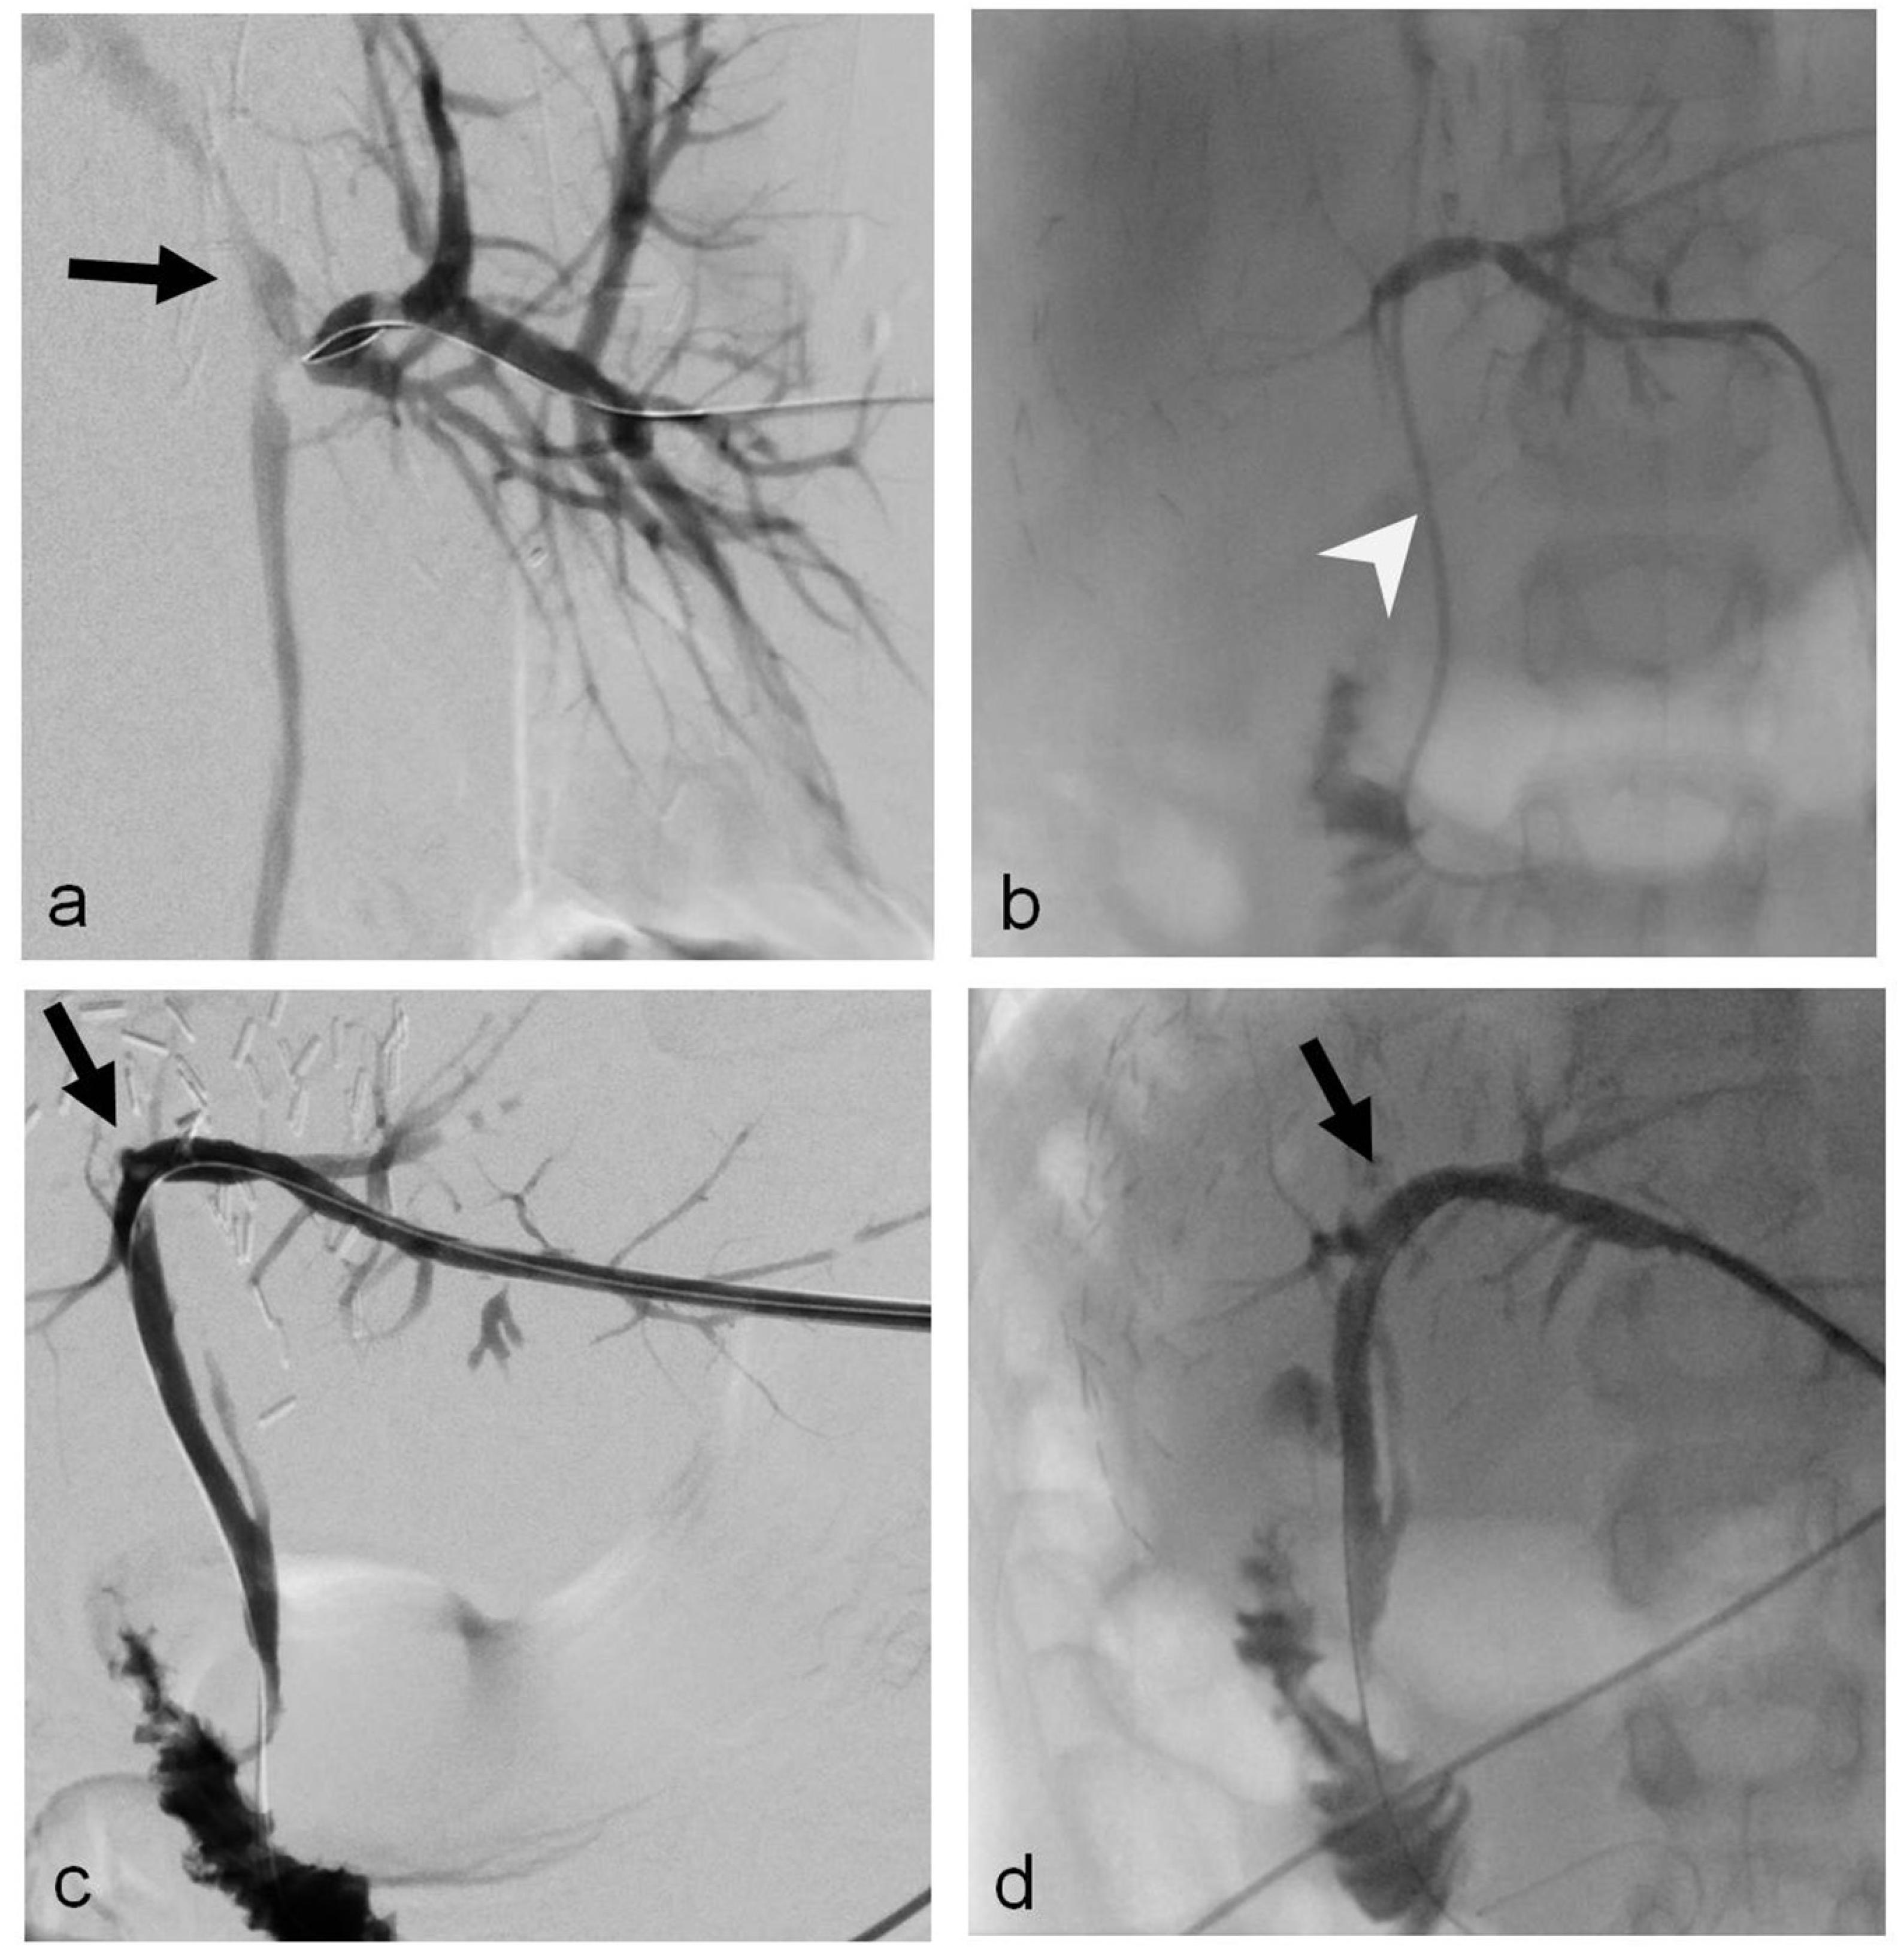

2.2. Procedure Technique

- Uller, W.; Wohlgemuth, W.A.; Hammer, S.; Knoppke, B.; Goessmann, H.; Loss, M.; Schlitt, H.J.; Stroszczynski, C.; Zorger, N.; Heiss, P. Percutaneous treatment of biliary complications in pediatric patients after liver transplantation. Rofo 2014, 186, 1127–1133. [Google Scholar] [CrossRef]